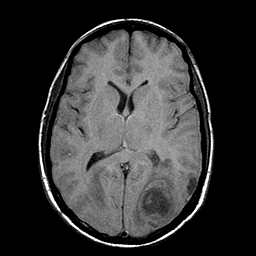

Sarcoma, MR Study #1 mr-t1 -- Slice #12

[Home][Help][Clinical] Slice 12